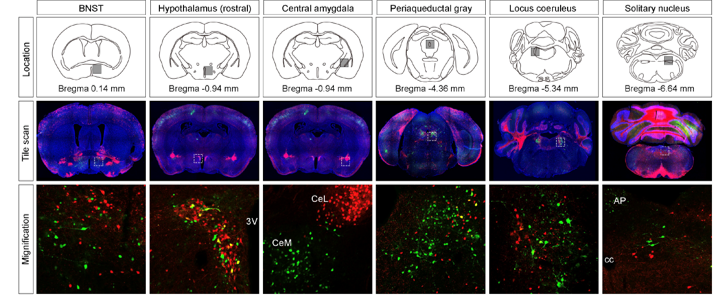

신경면역학 실험실(Neuroimmunology Laboratory)은 신경계와 다양한 말초조직 간의 상호작용을 연구합니다. 특히 말초조직 또는 면역세포를 조절하는 자율신경 신경회로를 발굴하고 작용기전을 밝힘으로써, 대사장애, 만성 염증성 질환, 종양, 근감소증 등을 극복하는 연구를 수행합니다.

뇌-말초조직 네트워크 규명을 위한 신경회로 발굴 및 제어연구

신경계-면역계 상호작용 연구